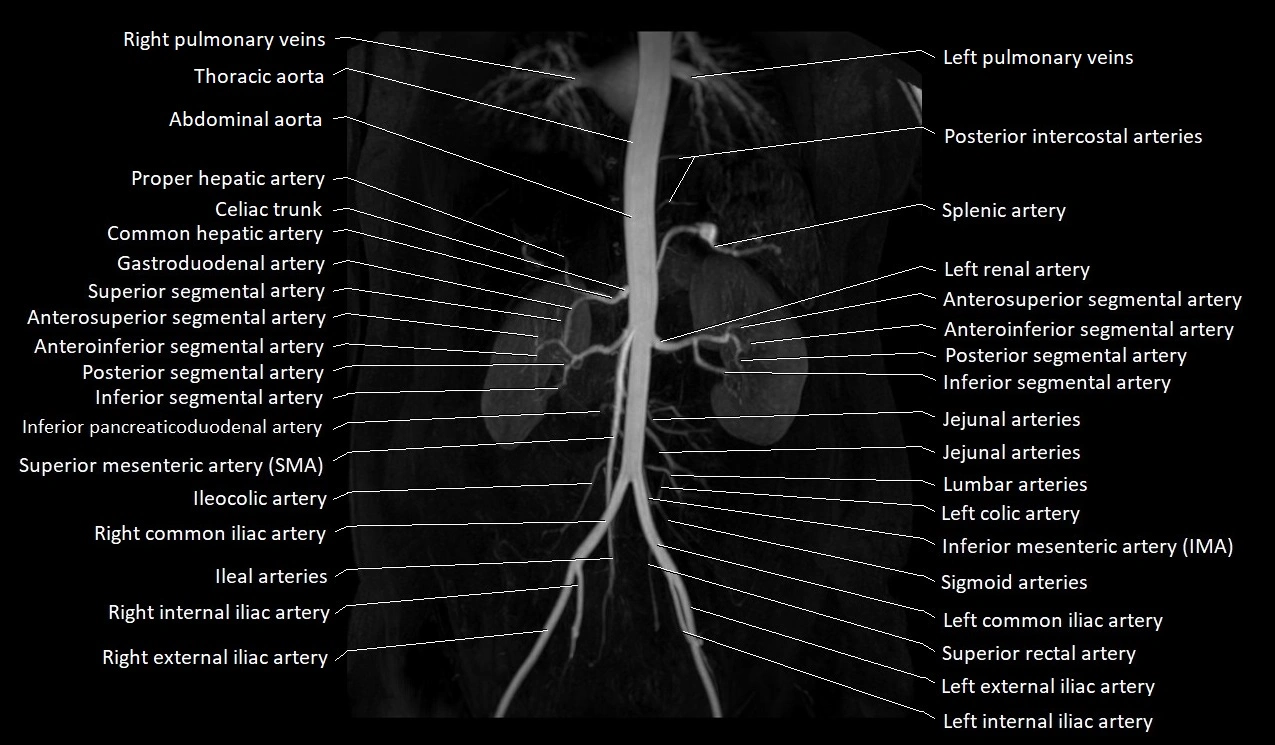

CT images

image